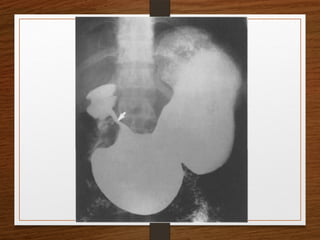

Doubt about the

diagnosis on the plain

radiographs

Contrast enema

• Features seen at the point of torsion include a

smooth, curved tapering of the colonic lumen, like a

hooked beak (the bird of prey sign)

• the mucosal folds often show a ‘screw’ pattern at the

point of twist

Sigmoid volvulus The invertedU-shaped loop is usually massively distended Commonly devoid of haustra, an important diagnostic point. The ahaustral margin can often be identified overlapping respectively  the lower border of the liver shadow (the liver overlap sign),  the haustrated, dilated descending colon (the left flank overlap sign)  the left side of the pelvis (the pelvic overlap sign). The top of the sigmoid volvulus usually lies very high in the abdomen (above the level of T10) with its apex on the left side.

Signs  Grossly distendedloop of sigmoid colon  Coffee bean sign  Air – fluid ratio > 2:1  Lack of haustra  Apex above 10th thoracic vertebra  Liver overlap sign  Left flank overlap sign  Pelvis overlap sign  Bird of prey /twisted bird beak appearance

Doubt about the diagnosison the plain radiographs Contrast enema

Contrast enema • Featuresseen at the point of torsion include a smooth, curved tapering of the colonic lumen, like a hooked beak (the bird of prey sign) • the mucosal folds often show a ‘screw’ pattern at the point of twist